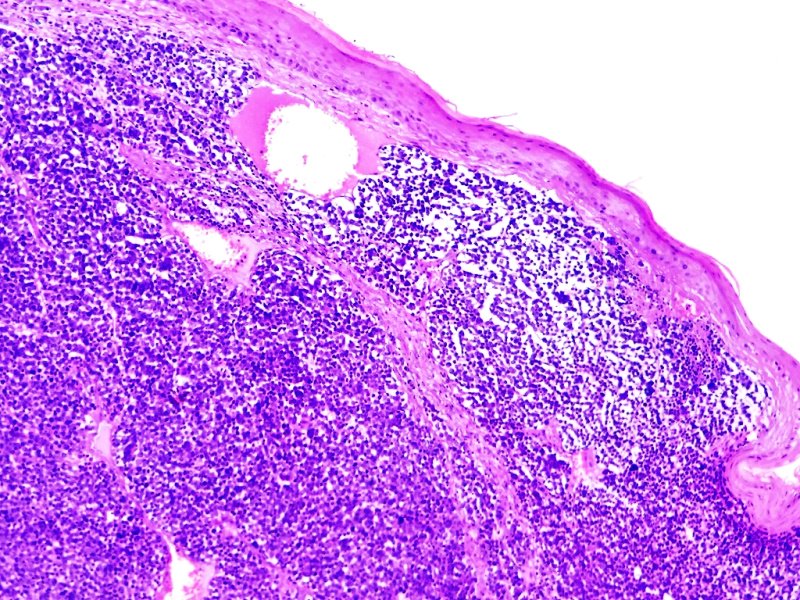

Anapat@Anapat_Lab·

Piel. Carcinoma decélulas de Merkel. Tinción HE